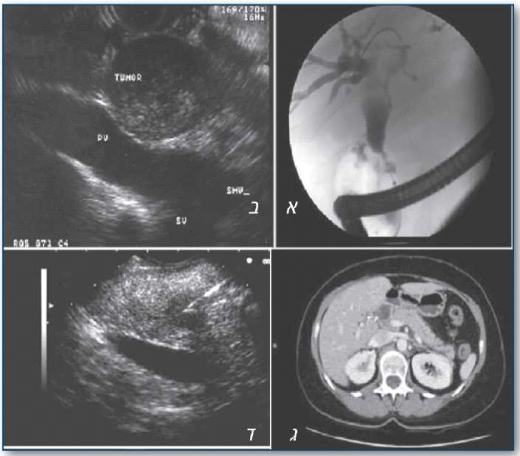

על-שמע שקיפתי (EUS)

בדיקת על-שמע שקיפתי משלבת שקיפה ו- US, וביכולתה לספק תמונות באיכות טובה של מערכת הלבלב ודרכי המרה באמצעות מתמר US המוחדר לקיבה או לתריסריון. תדירות מערכת ה- US נעה בתחום של 7.5-12 מגה-הרץ, ועומק החדירה מגיע לכדי 8-10 סנטימטרים. אפשר לקבל בבדיקה זו גם דגימת רקמה באמצעות FNA.

ל- EUS שיעורי דיוק גבוהים באבחון הגורם לחסימת דרכי המרה - שיעור רגישות של 97% וסגוליות של 88%. הדיוק גבוה באופן מיוחד באבחון אבנים בצינור המרה - רגישות של 95% וסגוליות של 96%. נתונים אלו טובים בהרבה מהנתונים המיוחסים ל- US דרך דופן הבטן ול- CT, ושווי ערך, אם לא טובים יותר, מאלו של ERCP או MRCP.

EUS יעיל במיוחד באבחון אבנים קטנות בצינור המרה, גם כאשר הצינור אינו מורחב במיוחד. כמו כן, EUS נמצא יעיל ביותר בהבדלה בין סוגים שונים של חסימה ממארת. הדיוק המושג בשילוב של בדיקת EUS עם FNA של מסה לבלבית-מרתית מגיע ליותר מ- 80%, והדיוק טוב יותר במסה לבלבית מאשר במסה מרתית. מחקרים פרוספקטיביים (Prospective studies) רבים מראים כי ל- EUS רגישות גבוהה יותר מאשר כל שיטות ההדמיה האחרות ובכללן CT (53-77%), US (50-67%), דימות תהודה מגנטית (MRI ,Magnetic Resonance Imaging) (50-67%) ו- ERCP (90%) באבחון גידול בלבלב. עליונות ה- EUS הייתה אף גבוהה יותר בגידולים הקטנים משלושה סנטימטרים. לכך יש חשיבות מכרעת בשל העובדה שחולים אלו ייהנו מניתוח בצורה הטובה ביותר.

כאשר מאובחן גידול בלבלב, יש לקבוע את דירוג ה- TNM של הגידול ורמת המפושטות שלו. לצורך קביעת דירוג ה- T וה- N של הגידול, ל- EUS עליונות על פני כל הבדיקות האחרות (80%-54=N ,94%-69=T). לצורך אבחון חדירה של הגידול לווריד שער הכבד (Portal vein), וריד הטחול (Splenic vein) ולאזור התכנסות וריד שער כבד ווריד מצע המעי העליון (SMV ,Superior Mesenteric Vein), שיעור הדיוק של EUS הגיע לכדי 87-95%, והיה עדיף על פני CT (41-75%), ודימות כלי דם (Angiography) (75-79%). עם זאת, הדיוק של EUS נמצא נמוך יותר באבחון מעורבות ה- SMV וכלי הדם העורקיים.

תהודה מגנטית של דרכי המרה והלבלב (MRCP)

בדיקה זו מבוצעת בשיטה שנועדה להגביר את האות המתקבל מנוזלים הנמצאים בצינורות המרה והלבלב, ללא שימוש בחומר ניגוד או קרינה מייננת. עיבוד ממוחשב של התמונות המתקבלות מספק תמונה תלת-ממדית של צינורות המרה.

טומוגרפיה ממוחשבת סלילית (hCT) וכולנגריוגרפיה סלילית (hCTC)

hCTC מאפשרת הדגמה של צינורות המרה והערכה של מבנים מחוץ לצינורות המרה בשלבים שונים: שלב עורקי, ורידית ופרנכימטי. הדיוק של hCTC בגילוי ומיקום חסימה חוץ-כבדית של דרכי המרה מגיע לכדי 81-94% ו- 88-92% בהתאמה. ברוב המקרים בדיקת CT שגרתית מסוגלת לגלות את סיבת החסימה ברמת דיוק גבוהה של 70-94%.